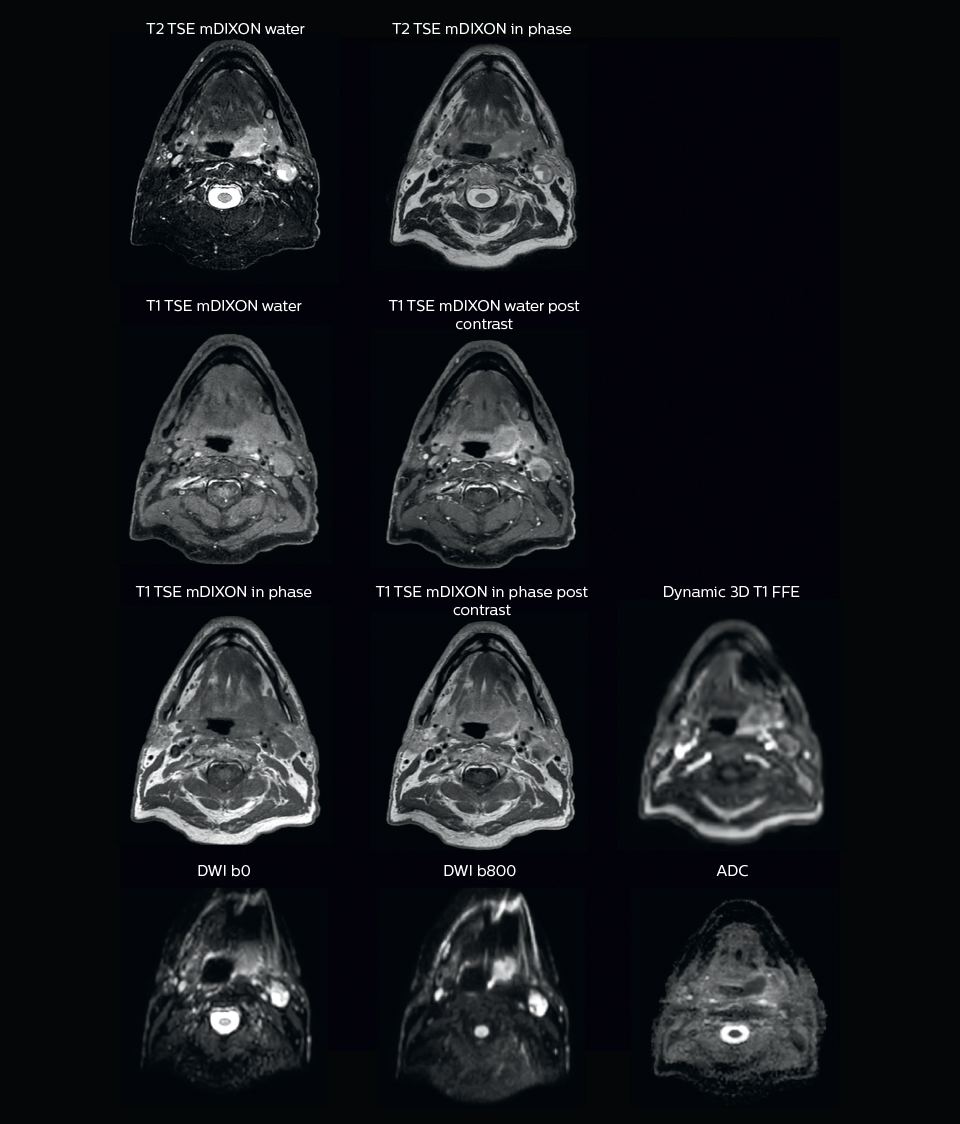

“We use pre- and post-contrast T1- and T2-weighted sequences with the fast and robust mDIXON method for fat suppression,” says Dr. Philippens. “Dynamic contrast-enhanced imaging is performed with high temporal resolution and low spatial resolution, to see the contrast agent uptake in the tumor. Diffusion weighted imaging is used qualitatively to see how the tumor extends into another structure, rather than for strict delineation.”

“When we can visualize intraprostatic lesions, the radiation therapist can then plan to boost them, giving a higher dose to those lesions instead of giving a uniform dose to the whole prostate, in the hope to better treat the patient and have less risk of recurrent tumors. However, this is not yet clinical routine. For visualizing the lesions, we not only use anatomical, T2-weighted imaging, but also diffusion weighted MRI and dynamic contrast- enhanced MRI."

“On the T2-weighted MRI with fat suppression the tumor with its edematous surrounding tissue can be clearly distinguished. This is particularly useful if the tumor does not show enhancement after contrast injection.

“Diffusion weighted imaging (DWI) shows very high contrast between the tumor and surrounding tissue. DWI helps us to see how a tumor extends into another structure, which we may not see on the T1-weighted or T2-weighted images. However, as DWI images are prone to distortions, these are mainly used to visualize the tumor and for response assessment, and not yet so much for delineation. I like to include diffusion weighted imaging, as it is so easy to see the tumor in these images. In my opinion, it has great potential, both for supporting tumor delineation and in response assessment.”